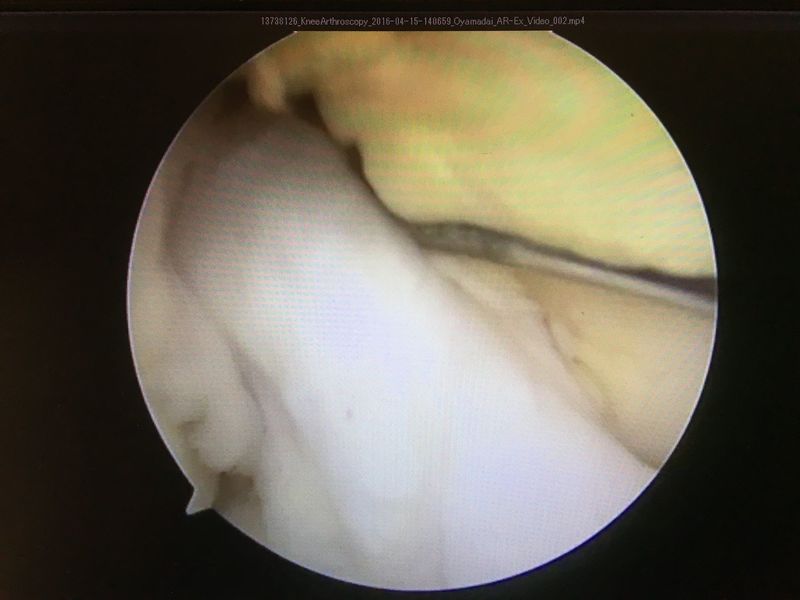

手術所見

![]() | ![]() | ![]() |

| ACLは緊張がなく機能していない | 外側半月板は問題なし | 内側半月板は問題なし |